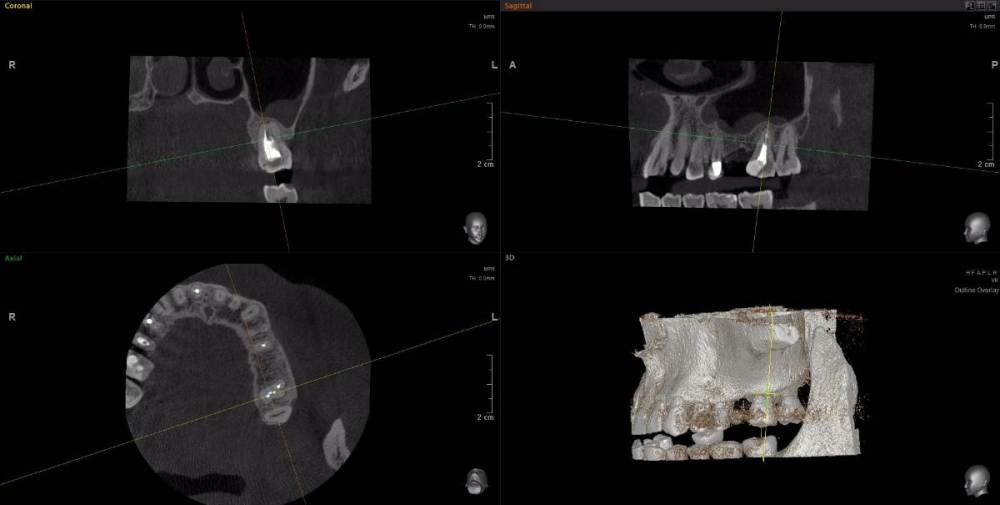

wladdX Опубликовано 15 апреля, 2021 Поделиться Опубликовано 15 апреля, 2021 Несколько скриншотов из вашей КЛКТ. Зуб 25: Зуб 27: Правая сторона: 1 Ссылка на комментарий

red_butler Опубликовано 16 апреля, 2021 Поделиться Опубликовано 16 апреля, 2021 1.5 1.6 перелечивать, 2.4 похоже кариес корня, нужно смотреть очно, 2.5 парадонтологическое поражение, смотреть очно, 2.6 ревизия корневых каналов Ссылка на комментарий